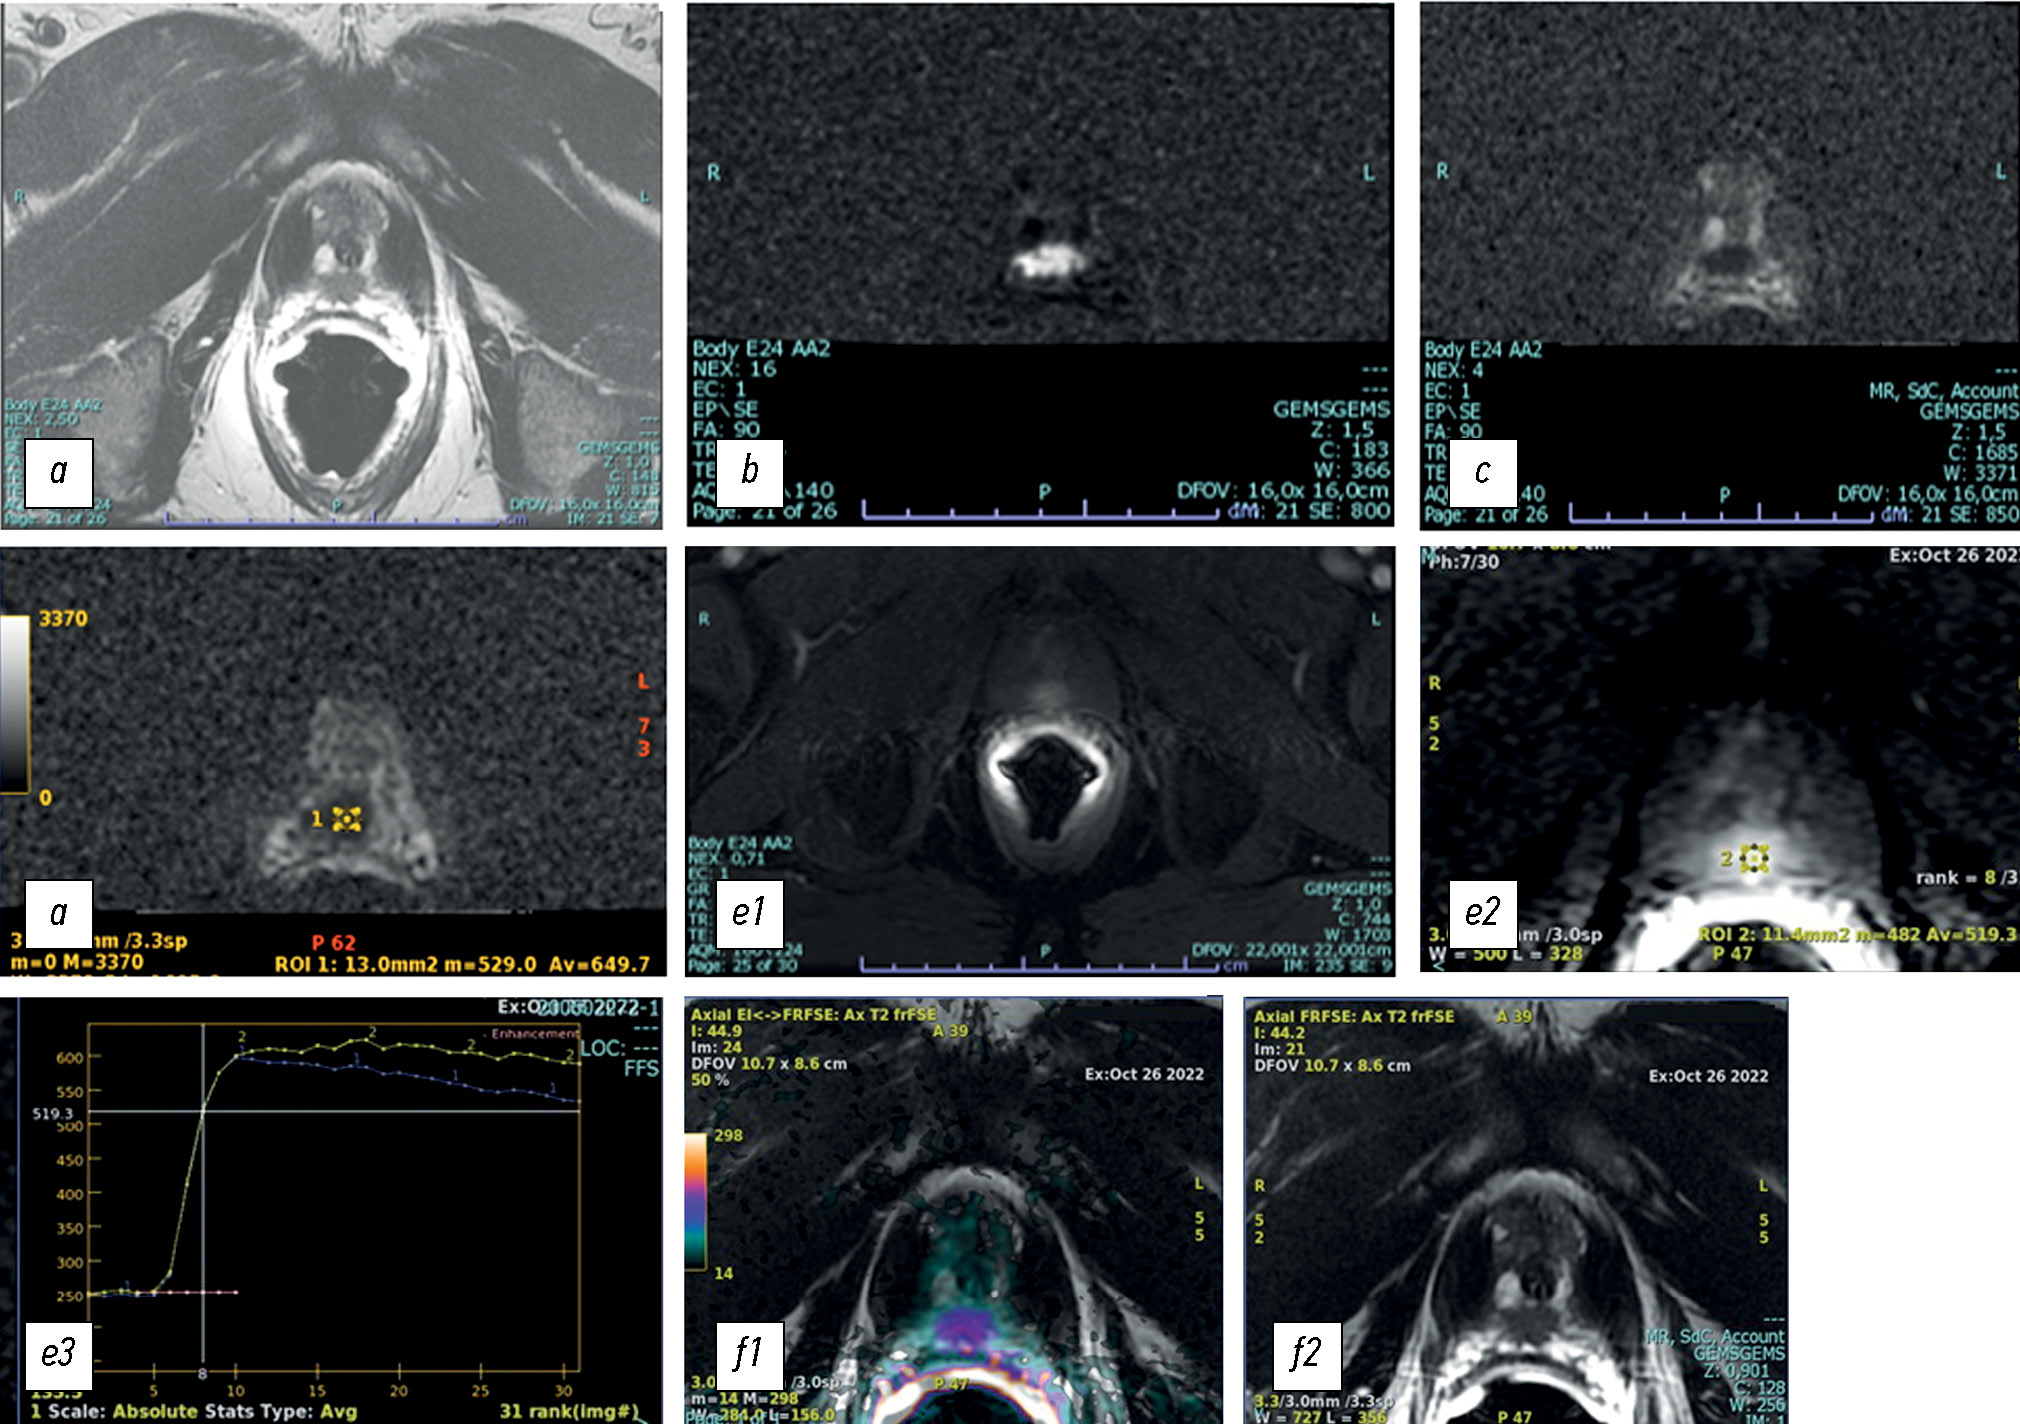

Multiparametric magnetic resonance imaging and magnetic resonance imaging fusion-guided biopsy for the diagnosis of prostate cancer: current status

This review explains the role of multiparametric magnetic resonance imaging, particularly in prostate biopsy, in the detection of prostate cancer. The use of multiparametric magnetic resonance imaging in the diagnosis of prostate cancer has also allowed its use in magnetic resonance imaging-guided biopsies, which according to many studies present high sensitivity and specificity in early diagnosis and staging, in patients with persistently high prostate-specific antigen levels despite previous negative prostate biopsies, and in the follow-up of patients under active surveillance.

To perform a targeted prostate biopsy, three types of magnetic resonance imaging guidance are available: cognitive fusion, direct magnetic resonance imaging-guided biopsy performed within a tomograph (in-bore biopsies), and software coregistration of stored magnetic resonance images with real-time ultrasound using a fusion device, with multiparametric magnetic resonance imaging findings digitally overlaid on real-time transrectal ultrasound images for targeted biopsy.

Each method has its advantages and disadvantages. Magnetic resonance imaging-targeted biopsy improves the quality of histological results compared with other approaches, with approximately 90% correct detection of significant index lesions. Correct staging allows the selection of the best therapeutic options, adequate evaluation of the prognosis, and reduction of the incidence of new biopsies and complications. The current objective is to make magnetic resonance imaging-guided biopsy increasingly available and standardize the technique to minimize inter-operator variability depending on the available system.